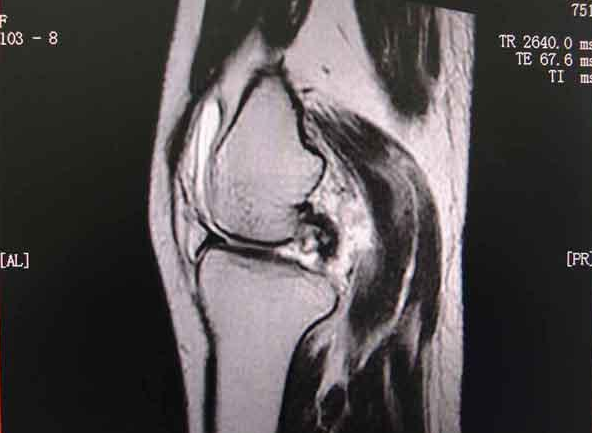

这项不寻常的研究对半月板撕裂患者进行了调查。半月板是月牙形的软骨,有助于为膝盖提供缓冲和稳定性。该研究称,在美国,半月板关节镜手术是最常见的骨科手术,每年约进行70万台,据估算费用高达40亿美元(约合人民币242亿元)。

这种手术称为关节镜半月板部分切除(arthroscopic partial meniscectomy),需要在患者身上打开小切口,伸入关节镜,让医生看到里面的情况,并用工具对撕裂的半月板进行剪切,再把剩下部分的粗糙边缘修剪光滑。

在芬兰开展的这项研究并不是说手术没有用;目前的共识是,在某些情况下应该对患者进行这种手术,尤其是年轻患者和急性运动损伤造成的撕裂。但约80%的撕裂是磨损和老化造成的,一些研究人员认为,在这些情况下,应该严格限制这种手术。